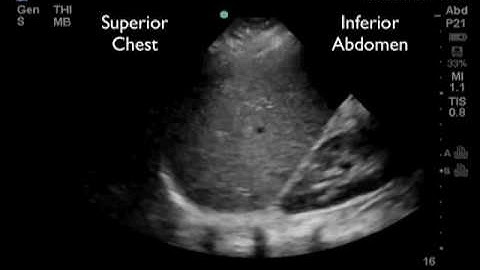

FAST Exam Part 1: RUQ Evaluation